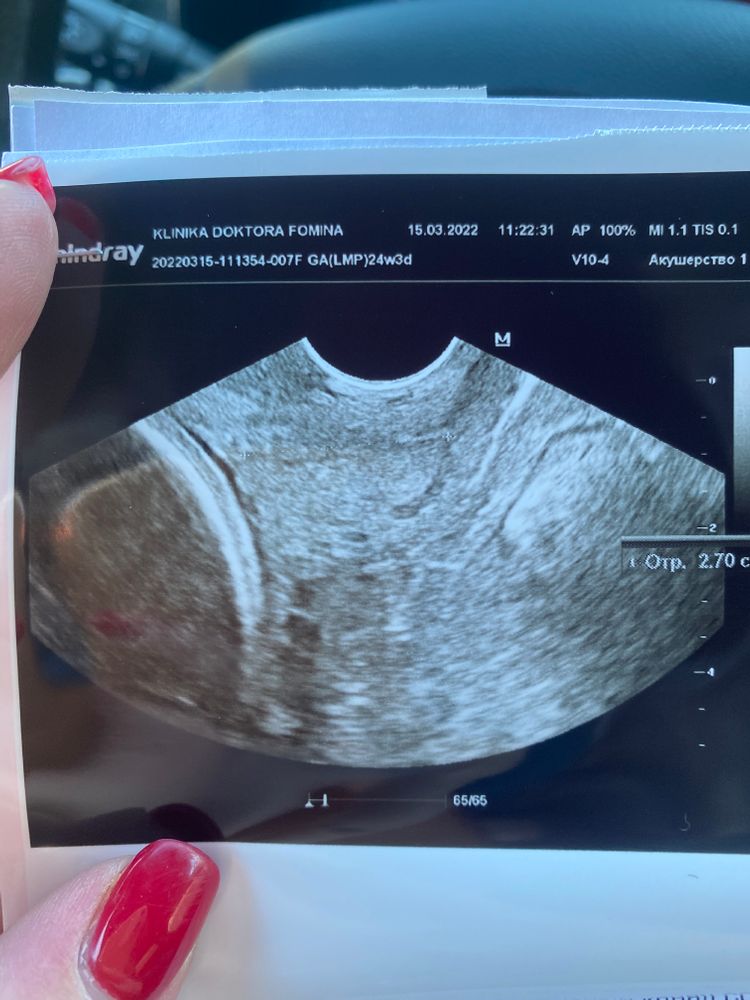

Шейка 27 мм на 25 недели …ваши истории

Девочки , мерю шейку каждые 7-10 дней и вот сегодня она 27мм. Последние недели держалась 33,8-30,04 ( последние недели 30-31). Отправили в стационар , сказали будут капать и смотреть в динамике . И скорее всего ставить пессарий , эффективен ли он ? Реально ли доносить беременность ? Шейка закрытая, малыши оба давят на шейку . А перед измерением резало дня два во влагалище .